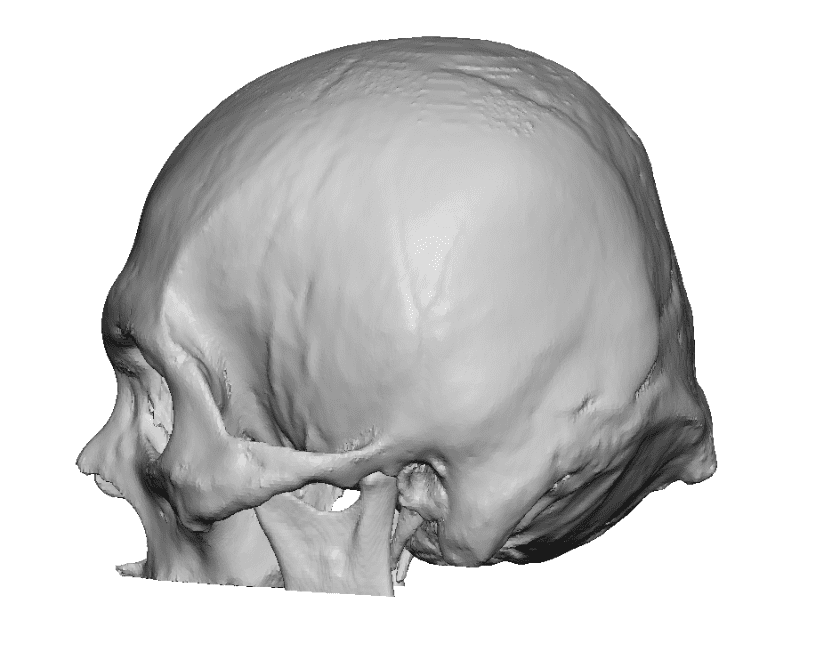

Patient 28

Desire for rounder shape to the top of the head from a congenital parasagittal deficiency skull shape.

Custom skull implant designed to fill in the parasagittal deficiencies.

Desire for rounder shape to the top of the head from a congenital parasagittal deficiency skull shape.

Custom skull implant designed to fill in the parasagittal deficiencies.